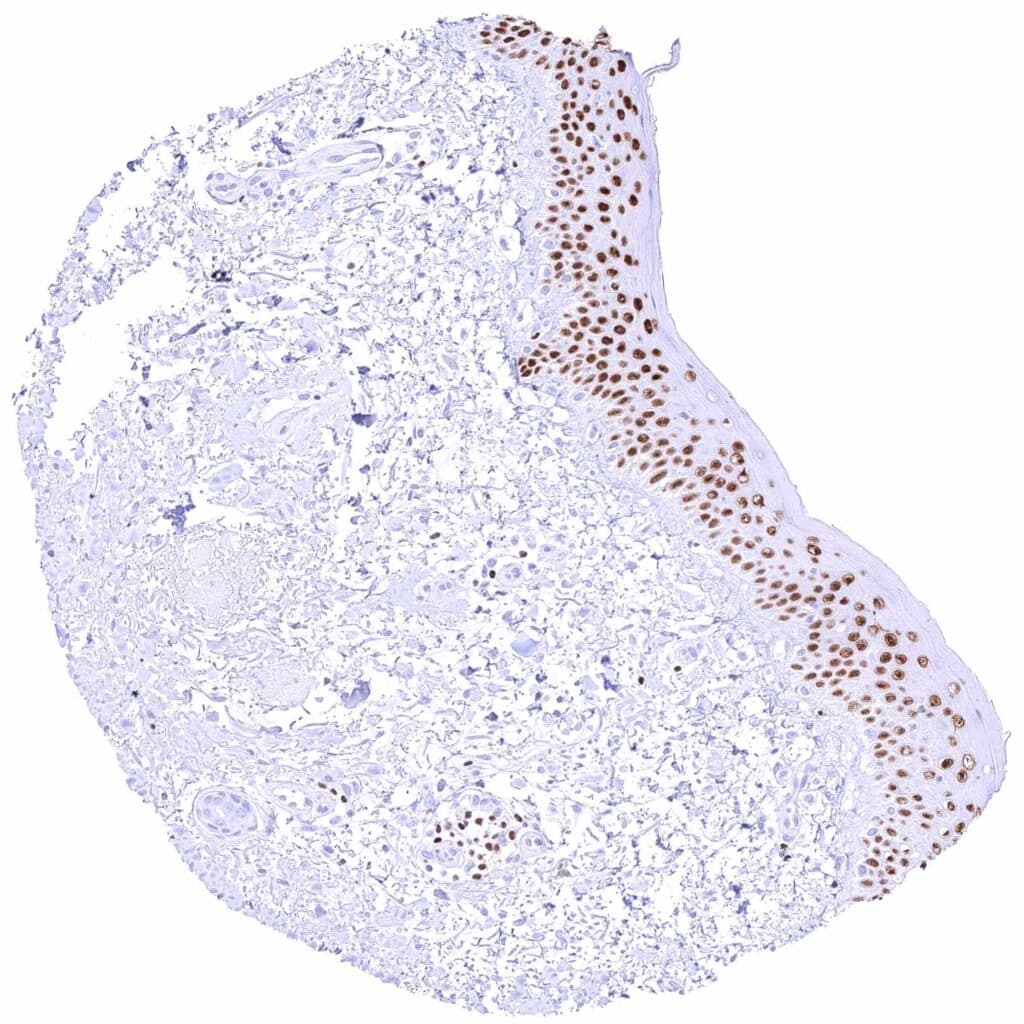

Skin – Strong nuclear GATA3 staining of squamous epithelial cells.